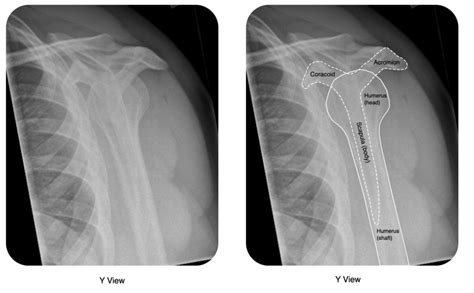

The primary goal of an X-ray in this scenario is to confirm whether a dislocation has occurred. A normal shoulder joint will show the head of the humerus (the ball) sitting neatly within the glenoid fossa (the socket). When a dislocation is present, the head of the humerus will be displaced, meaning it has popped out of the socket. The X-ray will clearly show this displacement. There are different types of shoulder dislocations, most commonly anterior (where the humerus moves forward) and posterior (where the humerus moves backward). The X-ray will help identify the direction of the dislocation, which is important for guiding treatment. It’s like having a map that shows exactly where the ball has rolled off the track. This visual confirmation is crucial for accurate diagnosis and planning the reduction (putting the shoulder back in place).